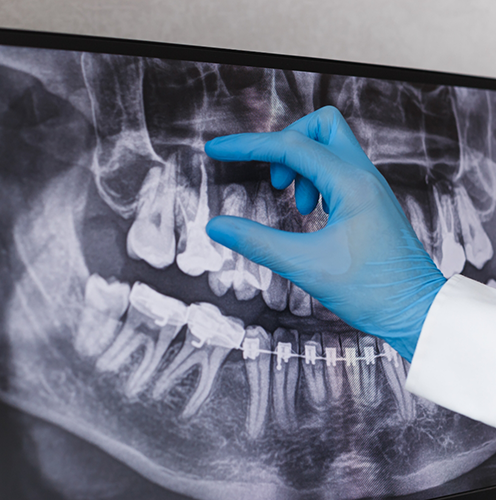

When a tooth is severely broken or infected beneath the gumline, is oddly-shaped, or has not fully erupted, a more involved approach is required. A complex extraction involves making a small incision in the gum tissue to access the tooth, and then often sectioning it into pieces for safer, less invasive removal. Dr. Sarcos has performed countless tooth extractions over the years, meaning that if it’s something she’s recommended for you, she’s well-suited for handling even the most challenging extractions with a strong emphasis on patient comfort.

Wisdom Tooth Extractions

Wisdom teeth often emerge during the late teens or early twenties and can cause crowding, pain, or infection when there isn’t enough space for them to properly erupt. Most people end up needing them removed, and the process of doing so is incredibly straightforward. At our office, Dr. Sarcos can perform gentle, precise wisdom tooth extractions to relieve your (or your teen’s) discomfort and protect your long-term oral health.